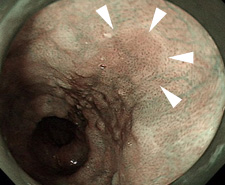

【早期食道がん】

通常観察